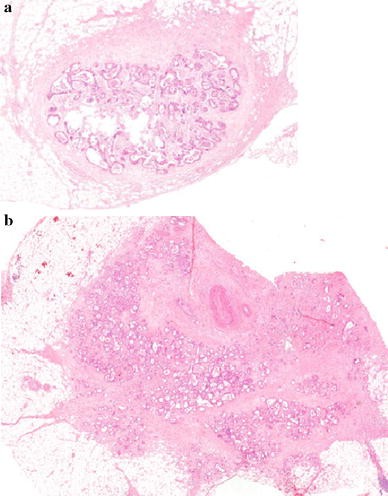

From stage II patients (n = 325) with reported ITDs, all available slides were reviewed by an independent pathologist who was unaware of clinical outcome. Apart from ITD characteristics, that is, number, size, shape (smooth or irregular, Fig. 1), presence of vasoinvasive and neuroinvasive growth were scored. Patients with a history of colorectal malignancy and those with irradical (macroscopically or microscopically) resections were excluded from the study. Patients with a follow-up period shorter than 3 months after surgery (due to death or lost in follow up) were excluded from the disease recurrence analysis.

Example of an isolated tumor deposit (ITD) with a smooth (a) and an irregular (b) contour